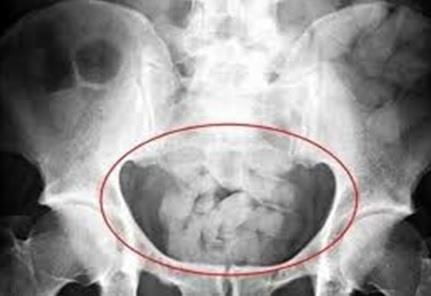

| Những thỏi Heroin được người "lạc đà" nuốt vào trong ruột. Ảnh: CCTV. |

Qua rà soát, cảnh sát tỉnh Hồ Nam tìm được nam thanh niên họ Phùng trong phòng một khách sạn thuộc huyện Tự Phổ, Hồ Nam. Lục soát căn phòng, điều tra viên tìm thấy một túi nylon đựng nhiều thỏi vật chất mềm kích thước 2 x 4 cm. Những thỏi này được bọc nylon cẩn thận và qua nhiều lớp, phân của thanh niên này chưa kịp xử lý còn dính trên sàn.

Phùng khai nhận đó là heroin được vận chuyển từ Myanmar về theo chỉ đạo của nghi phạm họ Đinh. Trước đó một ngày, Phùng đã nuốt những thỏi heroin vào cơ thể khi chuẩn bị nhập cảnh vào Trung Quốc. Hắn đã đại tiện ra 28 thỏi, trong cơ thể vẫn còn 32 thỏi. Khối lượng tổng cộng là 400 gram heroin tinh khiết được lấy ra từ Phùng.

Theo cảnh sát, việc mang theo những thỏi ma túy trong người là một hành động cực kỳ nguy hiểm, nếu nang ma túy bị vỡ thì người mang có thể sẽ mất mạng.